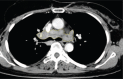

The aim of this study was to analyze the clinical, computed tomography (CT), and positron emission tomography (PET) findings of sarcoidosis, sarcoid reaction, and malignant lymph nodes (LNs) to the results of transbronchial LN aspiration and biopsy (TBNA).The TBNA results of mediastinal and hilar LNs of 152 patients in our hospital from July 2008 to March 2013 were retrospectively reviewed. Two independent radiologists measured the size and attenuation of LNs on CT and assessed the probability of the 3 categories: sarcoidosis (n = 36), sarcoid reaction (n = 25), or malignant LNs (n = 91). The total volume and attenuation of LNs were measured using Image J (NIH). The median maximum standardized uptake value (maxSUV) of the 3 mediastinal and hilar LNs on PET/CT was obtained.There was no significantly different CT finding between sarcoidosis and sarcoid reaction. Multivariate analysis showed that the age, total volume of LNs, and number of enlarged LNs significantly differed between sarcoid reaction and malignant LNs. Sarcoid reaction tends to be occurred in young patients (P = 0.007), the total volume of LNs was smaller (P = 0.04) than that of malignant LNs, and there were significantly more LNs >1 cm (P = 0.005). The median maxSUV of the 3 highest SUVs of the LNs did not significantly differ between the 3 entities.